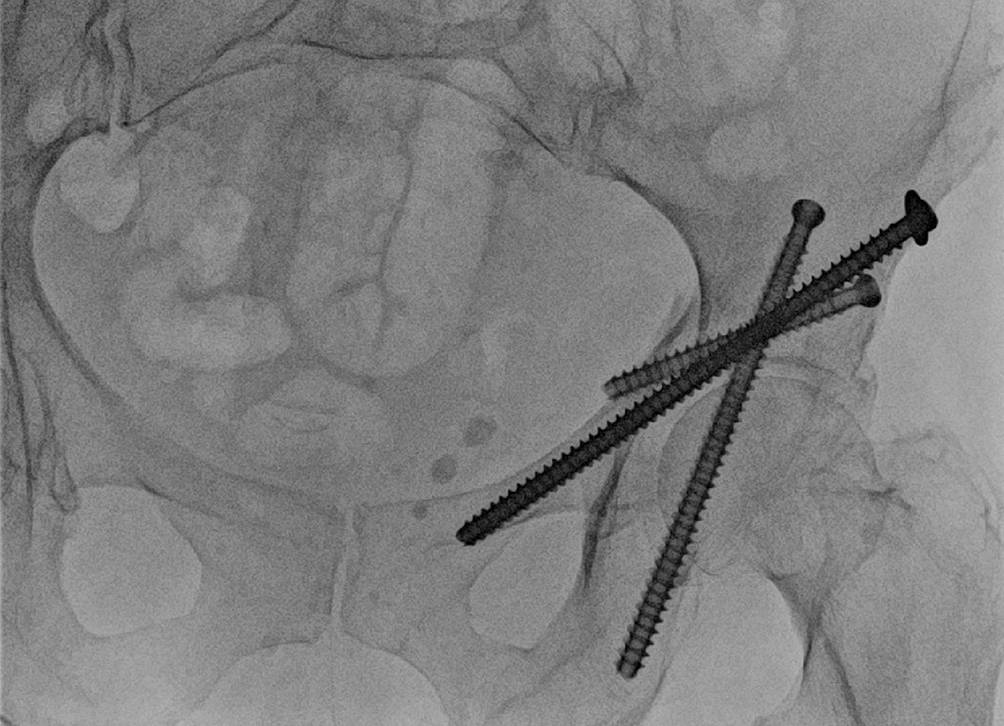

Abb. 12

Das intraoperative Bild nach Schraubenimplantation zeigt die korrekte Schraubenlage bei Fixierung aller Fragmente. Eine intraartikuläre Lage der Schrauben kann im Röntgenbild nicht suffizient ausgeschlossen werden, weshalb dies bereits im intraoperativen 3‑D-Scan durchgeführt wird